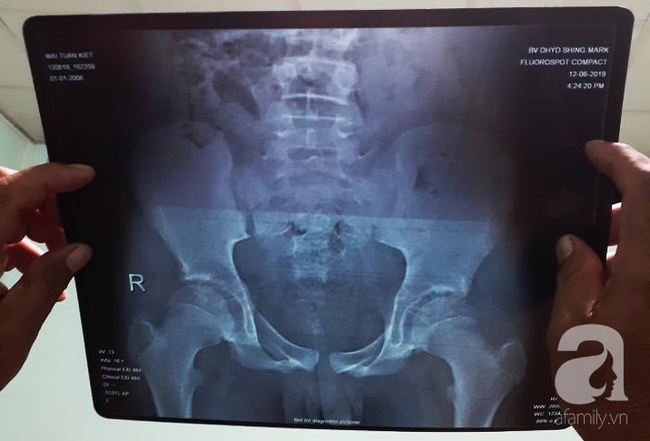

Hồ sơ bệnh án ghi nhận vào ngày 12/6 bé M.T.K bị xe tải tông, đau vùng hông lưng phải và tỉnh táo. Bệnh nhi được đưa vào BV Đại học Y Dược Shing Mark (TP Biên Hòa) thăm khám, chụp X-Quang chẩn đoán bé gãy trật xương chậu rồi chuyển lên bệnh viện Nhi đồng Đồng Nai (BV NĐĐN).

BV cũng đã cho bệnh nhân siêu âm đại tràng, ruột, gan, lách và kết quả không có gì bất thường. Do phía BV Shing Mark vừa chụp hình X-Quang cho bé nên nơi này không chụp lại.

"Gãy là tổn thương xương nhưng trên phim chỉ thấy đụng dập là tổn thương phần mềm. Bệnh nhân không gãy trật xương như chẩn đoán ban đầu từ BV Shing Mark" – đại diện BV giải thích.

Cụ thể, trong báo cáo BV gởi đến Sở Y tế tỉnh Đồng Nai về vụ việc nêu rõ chẩn đoán lúc ra viện vào ngày 17/6 là viêm ruột thừa xung huyết/chấn thương khung chậu: Gãy mào chậu phải, gãy khớp cùng chậu phải, sốc vagal, tổn thương đa cơ quan, nhiễm trùng huyết.

Sau khi xem các chẩn đoán lâm sàng và phim chụp X-Quang, vị bác sĩ khẳng định chắc chắn bệnh nhi này có tổn thương gãy xương.

"Nói bé bị viêm ruột thừa là chống chế, vì viêm ruột thừa sau chấn thương khung chậu là vô cùng hy hữu. Khả năng cao là bé đã gãy xương và bị thủng tạng rỗng gây nhiễm trùng viêm phúc mạc. Xét nghiệm lâm sàng có giá trị trong trường hợp này là siêu âm và chụp CT.

Đây là ca tương đối phức tạp, vì trẻ em còn sụn tăng trưởng ở các đầu xương gần các khớp xương. Do đó nếu không phải bác sĩ chuyên khoa chỉnh hình có kinh nghiệm thì nhìn phim X-Quang rất khó nhận ra tổn thương khung chậu" – bác sĩ phân tích.